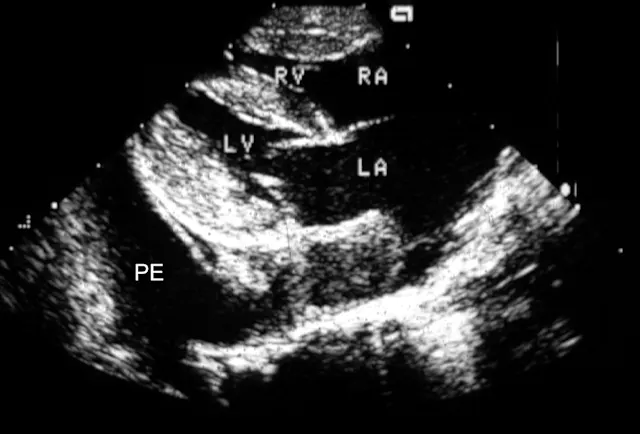

Once the patient is stabilized (often after 12 to 24 H), obtain radiographs (Figure 3) and echocardiography to confirm the diagnosis of CHF and to identify the nature and severity of the cardiac disease. The most common cause of CHF in cats is HCM; less common are dilated, restrictive, and unclassified cardiomyopathy. Murmurs associated with HCM are usually created by mitral regurgitation, abnormal displacement of the mitral valve during systole (systolic anterior motion or SAM), causing left ventricular outflow tract obstruction, or dynamic right ventricular obstruction either in combination (e.g., mitral regurgitation is always present with SAM) or alone (mitral regurgitation can also occur without SAM) (Figure 4).

FIGURE 4A Two-dimensional, right parasternal, long-axis view of the heart in a cat with HCM and pleural effusion. Note the large thrombus in the left atrium